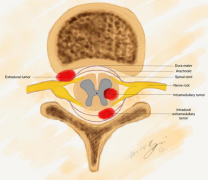

硼中子俘获疗法(BNCT)或成脊髓肿瘤放疗新选择

硼中子俘获疗法(BNCT)可以在癌细胞和正常细胞之间进行“筛选”,相较普通放疗手段更具针对性,因此为脊髓肿瘤的放疗提供了新的选择

硼中子俘获(BNCT)可以治疗脊髓肿瘤吗?

近期,很多患者都在讨论BNCT治疗脑肿瘤的可行性,那么,这项新的技术是否已经发展完善?国内患者何时能接受治疗